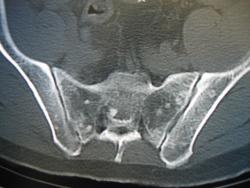

Диффузно в позвонках. Изображениекостях таза очаги локального остеосклероза? метастазы?

Я не занимаюсь КТ, МРТ и СКТ. Но весьма похоже на секундарные изменения. Каков возраст пациента, с чем направлен на исследование, НА ЧТО ЖАЛУЕТСЯ?

Жалоб нет. Возраст 45 лет, направлен на кт по поводу диф.диагностики очаговых изменений печени. А что  такое секундарные изменения?

Метастазы.

Сегодня уролог исключил рак простаты,фгдс,колоноскопия тоже чисто. Вопрос откуда мтс, если это они. У нас онкология вообще не берет пациентов для диф.диагностики."она" занимается только лечением рака поставленного в общей сети. пациента к ним отпускать нихочу(жалко)

Коллега произведите пациенту качественную рентгенограмму органов грудной полости и костей таза.

А что это может быть еще, если не метастазы -в тазовых костях, крестце и позвонках?

А если к этому прибавить обнаруженные изменения в печени?

На мой взгляд пациентом должны прицельно заняться именно онкологи.